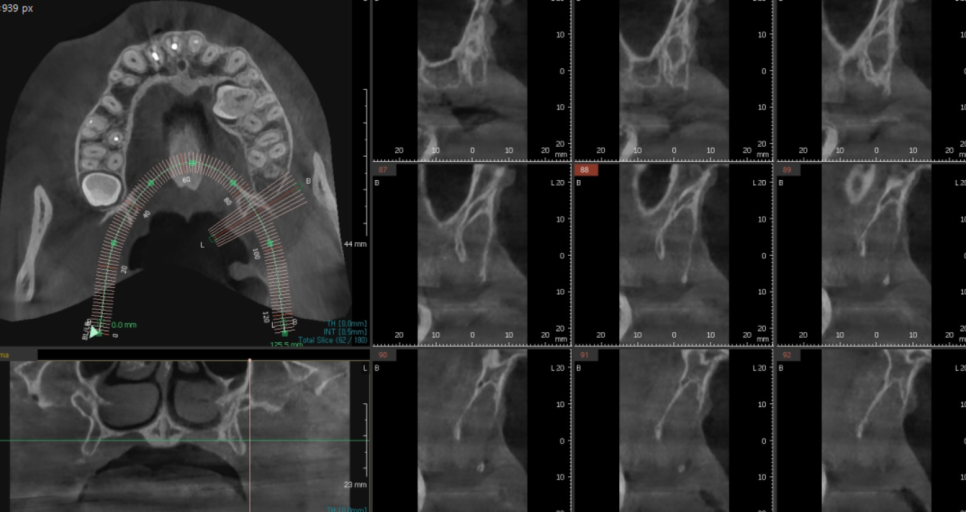

23.07.24

ct를 통해 매복치아 위치를 파악하고

어떻게 교정 발치하면 좋을지

머릿속에 그리고 발치에 들어갔습니다.

이제 제거를 해주어야겠죠~?